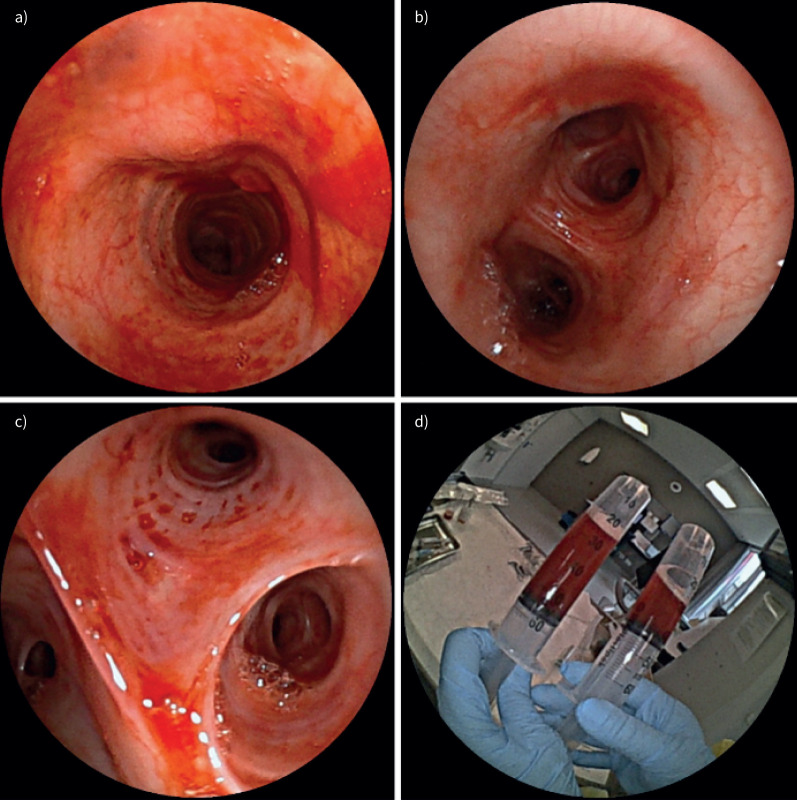

负压性肺水肿是术后患者急性呼吸窘迫的一个未被充分认识的原因。表现包括急性肺水肿和可能的DAH。及时认识和干预至关重要。https://bit.ly/4jYzOmn。

Negative pressure pulmonary oedema is an under-recognised cause of acute respiratory distress in post-operative patients. Presentations include acute pulmonary oedema and possibly DAH. Prompt recognition and intervention are essential. https://bit.ly/4jYzOmn.